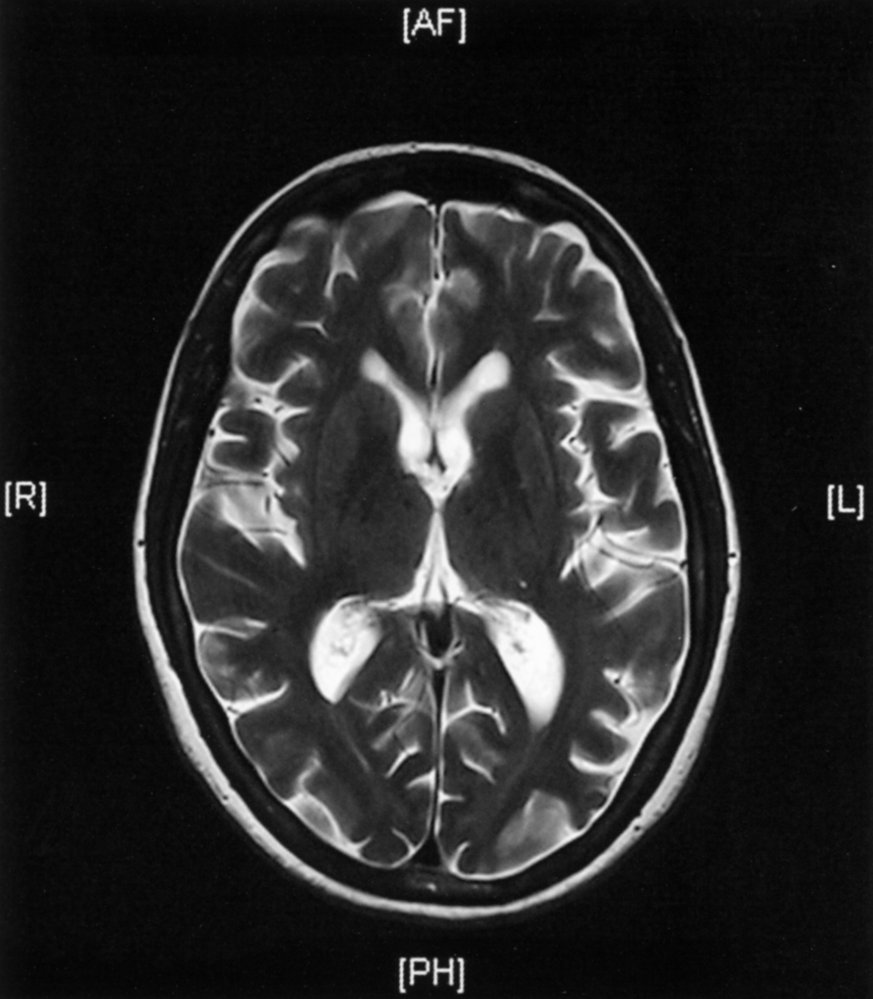

MRIbrain [7][8]

• Indication: all patients as part of the initial evaluation of major neurocognitive disorder

• Supportive findings

• Signs of generalized or focal cerebral atrophy

• Enlarged ventricles (ventriculomegaly)

• Narrowing of gyri

• Prominent cerebral sulci (hydrocephalus ex vacuo)

• Disproportionate atrophy of the medial temporal lobe including the hippocampi, amygdala, cingulate cortex, and parahippocampal gyrus